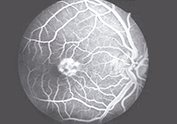

RETINOFLUORESCEINOGRAFIA (RFG)

Por medio de la inyección de un colorante, la fluoresceína, - se resaltan las alteraciones del fondo de ojo.